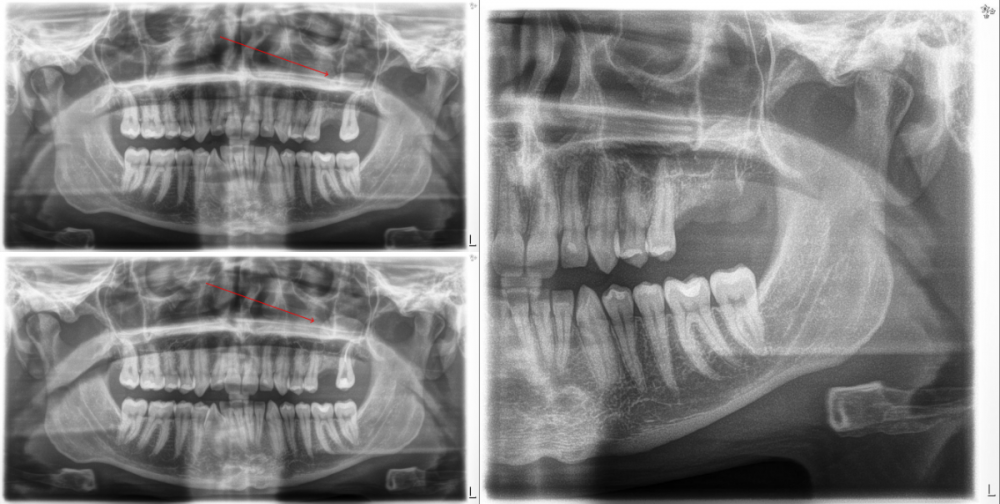

Первого декабря депульпированный зуб начал ныть. Сначала немного, но к пятому декабря так сильно разболелся, что мне пришлось поздней ночью, часа в два, отправиться в больницу — в отдел челюстно-лицевой хирургии. Там я показал доктору панорамный снимок, он увидел воспаление у корня того зуба и удалил его. Назначили антибиотики, я их пропил.

Сделал КТ и посетил хирурга, который удалял мне зуб. Врач сказал, что перфорации гайморовой пазухи нет и назначил противовоспалительные таблетки. Лучше, к сожалению, не стало: а сегодня так вообще отмечаю, что ныть стало гораздо сильнее.

Честно говоря, руки опускаются и это очень сильно бьёт по продуктивности. Сложно на чём-либо концентрироваться и чем-либо заниматься в принципе. Постоянная боль очень психологически выматывает. На первой фотографии панорамные снимки (до депульпации, после депульпации и после удаления зуба). На второй — КТ.

На КТ я вижу какое-то образование — видимо, киста. Ну, явно какое-то воспаление. Но вот, что интересно: сегодня я разглядел на панорамных снимках то же самое образование, то же самое воспаление! То есть, вероятно, тот зуб вовсе не нужно было удалять. Я связывал появление этой кисты с удалением зуба, но, видимо, оно было и до этого.